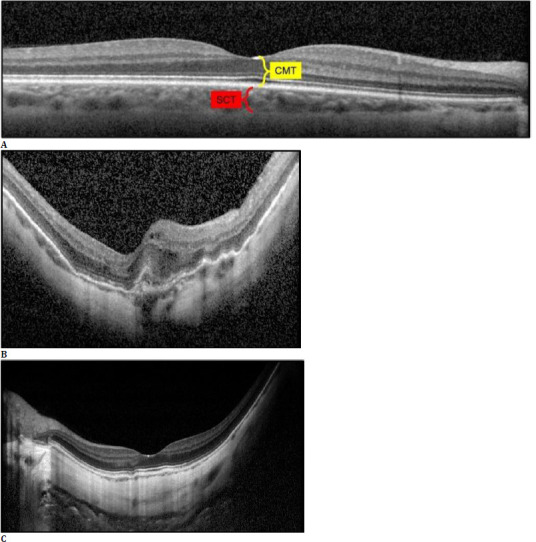

Materials and methods: A total of 122 eyes from 78 patients were included. Seventy-five eyes with an AL ranging between 26.00 and 27.49 mm comprised Group 1, and 47 with an AL of ≥ 27.50 mm comprised Group 2. Spectral-domain OCT was performed to measure the central macular thickness, subfoveal choroidal thickness (SCT) and swept-source OCTA was utilized to obtain the data on foveal avascular zone (FAZ) and vascular density (VD) values at the superficial and deep capillary plexuses (SCP and DCP), outer retina (OuR), and choriocapillaris (CC) segments.